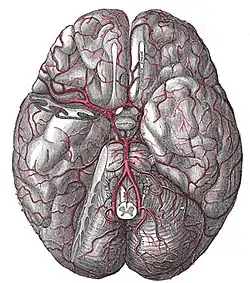

Blutversorgung des Gehirns

(Ansicht von unten, der rechte Schläfenlappen wurde teilweise entfernt)

Vier große Schlagadern versorgen das Gehirn des Menschen und der meisten Säugetiere mit sauerstoffreichem Blut (alte Bezeichnung: „arterielles Blut“). Je zwei liegen auf jeder Seite des Halses, vorn die inneren Halsschlagadern (Arteriae carotides internae) und hinten die Wirbelarterien (Arteriae vertebrales). Das Blut fließt nach der Passage des Gehirns über besondere venöse Hirnblutleiter (Sinus durae matris) ab, die gegenüber den Venen einige Besonderheiten aufweisen.

Nach dem Eintritt in den Schädel durch den Canalis caroticus zweigt aus der Arteria carotis interna jeder Seite ein Gefäß zum Auge (Arteria ophthalmica) ab. Nach Abgabe weiterer kleinerer Äste teilt sie sich in die Hauptstämme des vorderen Kreislaufs, die mittlere Hirnarterie (Arteria cerebri media) und die vordere Hirnarterie (Arteria cerebri anterior, bei Tieren als Arteria cerebri rostralis bezeichnet). Erstere versorgt die seitlichen (lateralen), letztere die der Mitte zugewandten (medialen) Teile der jeweiligen Großhirnhemisphäre mit Ausnahme von Teilen des Temporallappens und des gesamten Occipitallappens, die vom hinteren Kreislauf gespeist werden. Die tiefen Kerngebiete (Basalganglien, Thalamus) haben eine gemischte Versorgung. Die beiden vorderen Hirnarterien sind durch die sehr kurze Arteria communicans anterior miteinander verbunden.

Die Wirbelarterien in ihren Endsegmenten und die Arteria basilaris entsenden Äste zum Hirnstamm und Kleinhirn (A. cerebelli inferior posterior, A. cerebelli inferior anterior, A. cerebelli superior). Oberhalb der Brücke teilt sich die Arteria basilaris abermals und wird zu den beiden hinteren Hirnarterien, die sich in die Arteriae occipitales medialis bzw. lateralis teilen und die hinteren Bezirke des Großhirns sowie Teile des Zwischenhirns versorgen. Eine individuell unterschiedlich stark angelegte Arteria communicans posterior verbindet die hintere Hirnarterie jeder Seite mit der inneren Halsschlagader.

Verbindungen zwischen vorderem und hinterem Kreislauf

Die Arteria communicans anterior, der erste Abschnitt der Arteria cerebri anterior, ein kurzer Abschnitt der Arteria carotis interna, die Arteria communicans posterior und das erste Teilstück der Arteria cerebri posterior bilden, beide Seiten zusammen betrachtet, eine ringförmige Verbindung unter der Hirnbasis aus (Circulus arteriosus cerebri Willisi). Dieser Gefäßring stellt ein Anastomosensystem dar, das die Stromgebiete der Arteriae carotides internae und der Arteria basilaris anatomisch, aber funktionell nicht immer ausreichend miteinander verbindet. Grundsätzlich (das heißt bei ausreichender Adaptationszeit) kann er jedoch ermöglichen, dass ein einziges Hauptgefäß die gesamte Durchblutung des Gehirns aufrechterhält.